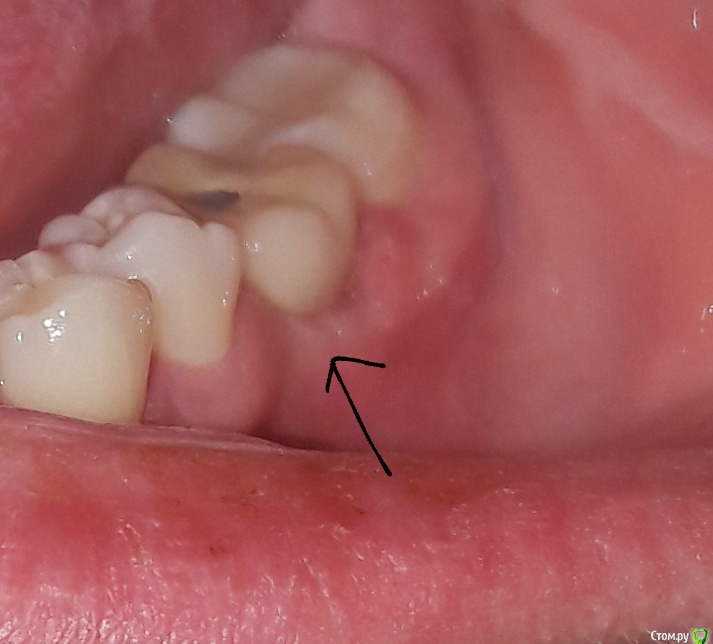

anasta.siiia1 Опубликовано 12 апреля, 2019 Поделиться Опубликовано 12 апреля, 2019 Здравствуйте всем! Поставили коронку 1 неделю назад. Между коронкой и десной забивается вся еда, которую я ем.(Овощи, фрукты, мясо и т.д). Именно со стороны щеки. Зуб 6-ой нижний слева.Ходила к своему стоматологу-ортопеду, сказал что ничего страшного в этом нет, это совершенно нормально, проблема решается зубной нитью, и плюс посоветовал преобрести ирригатор, проблем с десной нет и т.д и т.п. Так вот нитью я ничего не могу оттуда толком достать,только острым краешком зубочистки. И еда забивается настолько, что достовляет дискомфорт. Ощущения прям такие, как будто бы десна чем-то забилась плотно. Целую неделю так и живу с этим зубом, достаю эти куски еды. Даже щеткой не прочистишь. Ну и запах конечно от застрявшей еды, просто жесть...((( Буквально вчера воспалилась десна и идет гной оттуда... Ссылка на комментарий

krokomot Опубликовано 13 апреля, 2019 Поделиться Опубликовано 13 апреля, 2019 в области коронки с щечной стороны в пришеечной области отсуствует прикрепленная десна, её необходимо сформировать, делает это хирург-стоматолог владеющий пластикой десны. Коронку снять, провести пластику десны с формированием правильного контура и массива прикрепленной десны и будет вам счастье, снимок сделать и приложить к теме. Ссылка на комментарий